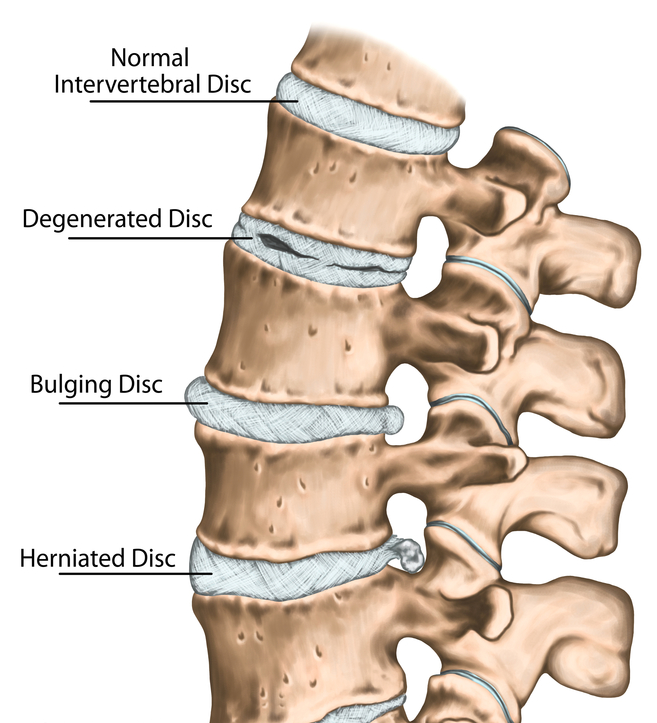

What is the difference between a bulging disc and a herniated disc?